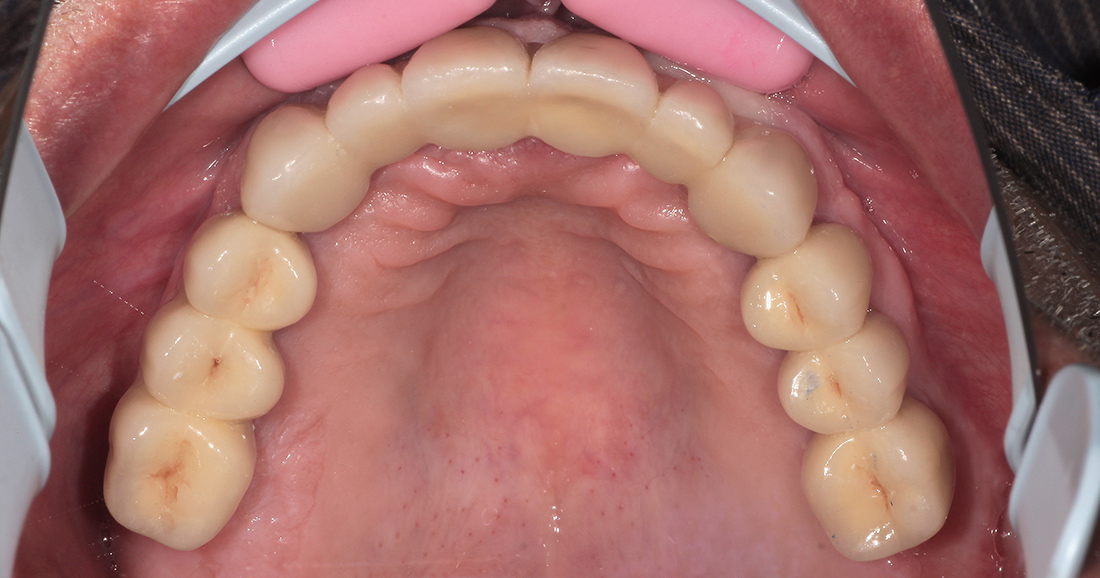

Окончательное протезирование было выполнено тремя металлокерамическими мостовидными конструкциями на верхней челюсти, мостовидным протезом внизу справа и отдельной коронкой на импланте в области шестого зуба нижней челюсти слева. Фиксация коронок проводилась на индивидуальные циркониевые абатмены одноэтапно.

Общий срок лечения составил порядка пяти месяцев.